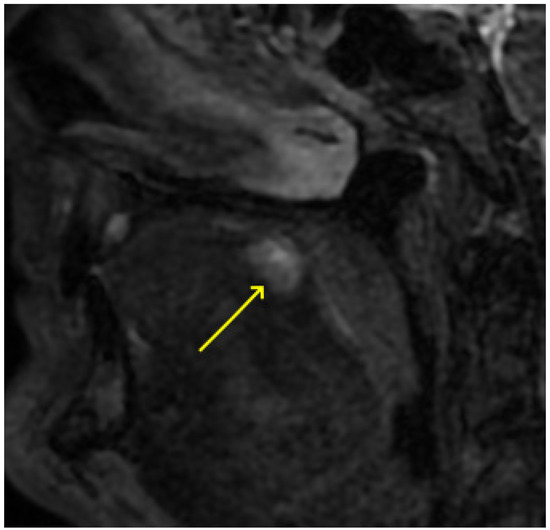

2. Detailed Case Description